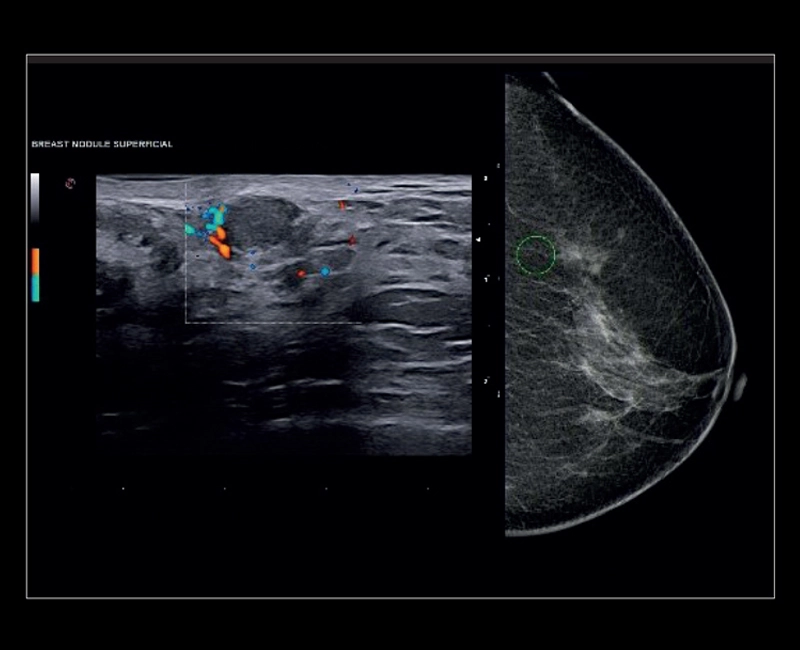

MyLab™9 Platform - Breast BodyMap and real-time ElaXto in Mammo

MyLab™9 Platform - Breast BodyMap and real-time ElaXto in Mammo